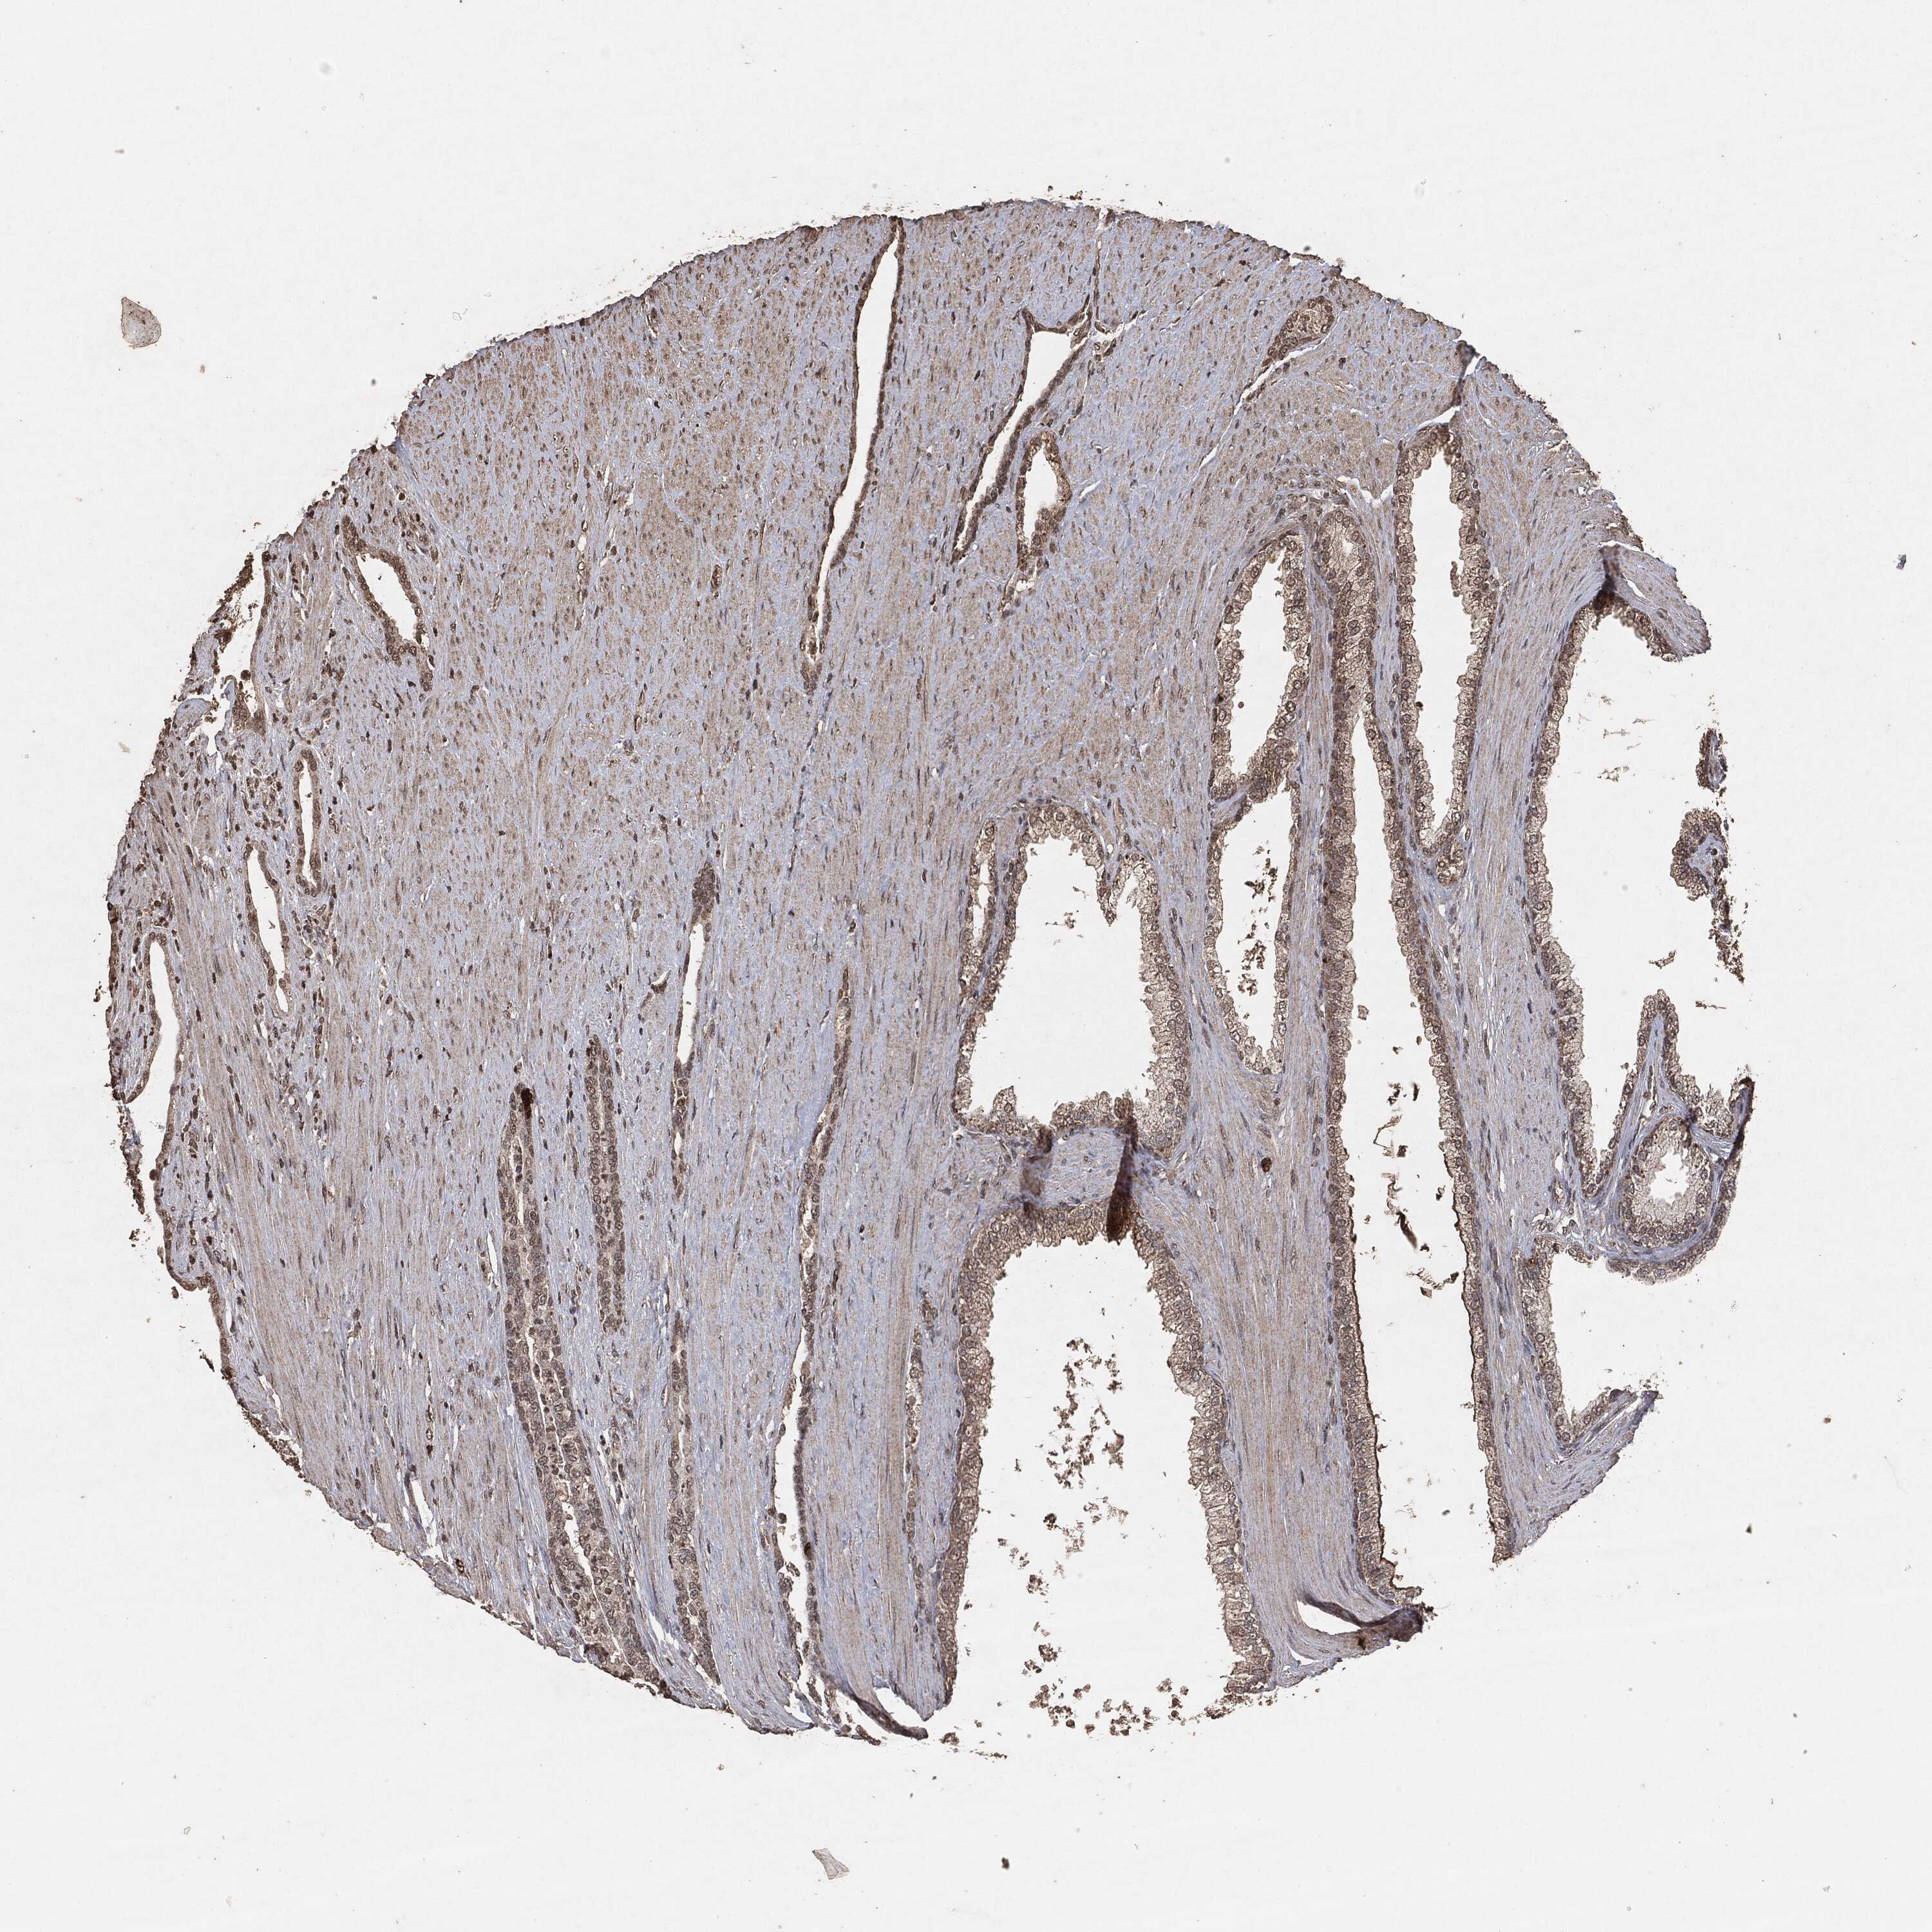

PROSTATE CANCER - Protein expressioni

A mouse-over function shows sample information and annotation data. Click on an image to view it in a full screen mode. Samples can be filtered based on level of antibody staining by selecting one or several of the following categories: high, medium, low and not detected. The assay and annotation is described here.

Note that samples used for immunohistochemistry by the Human Protein Atlas do not correspond to samples in the TCGA dataset.

Antibody stainingi

Antibody staining in the annotated cell types in the current human tissue is reported as not detected, low, medium, or high, based on conventional immunohistochemistry profiling in selected tissues. This score is based on the combination of the staining intensity and fraction of stained cells.

Each image is clickable and will lead to virtual microscopy that enables deeper exploration of all samples and also displays staining intensity scores, fraction scores and subcellular localization as well as patient and tissue information for each sample.

Adenocarcinoma, Medium grade

Adenocarcinoma, Low grade

Adenocarcinoma, High grade

Adenocarcinoma, NOS